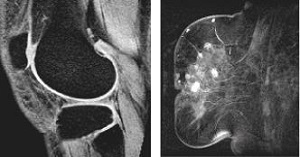

Use Chemical SAT to reduce the signal from competing tissue and to increase the conspicuity of pathology. Chemical SAT techniques are useful to suppress fat or water in your images, such as:

- Demonstrating musculoskeletal tumors when used with contrast agents

- Identifying fat by its dark appearance in fat-suppressed images